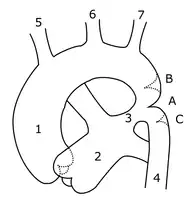

Sketch showing heart with coarctation of the aorta. A: Coarctation (narrowing) of the aorta. 1:Inferior vena cava, 2:Right pulmonary veins, 3: Right pulmonary artery, 4:Superior vena cava, 5:Left pulmonary artery, 6:Left pulmonary veins, 7:Right ventricle, 8:Left ventricle, 9:Pulmonary artery, 10:Aorta -

Schematic drawing of alternative locations of a coarctation of the aorta, relative to the ductus arteriosus. A: Ductal coarctation, B: Preductal coarctation, C: Postductal coarctation. 1: Aorta ascendens, 2: Arteria pulmonalis, 3: Ductus arteriosus, 4: Aorta descendens, 5: Truncus brachiocephalicus, 6: Arteria carotis communis sinistra, 7: Arteria subclavia sinistra -